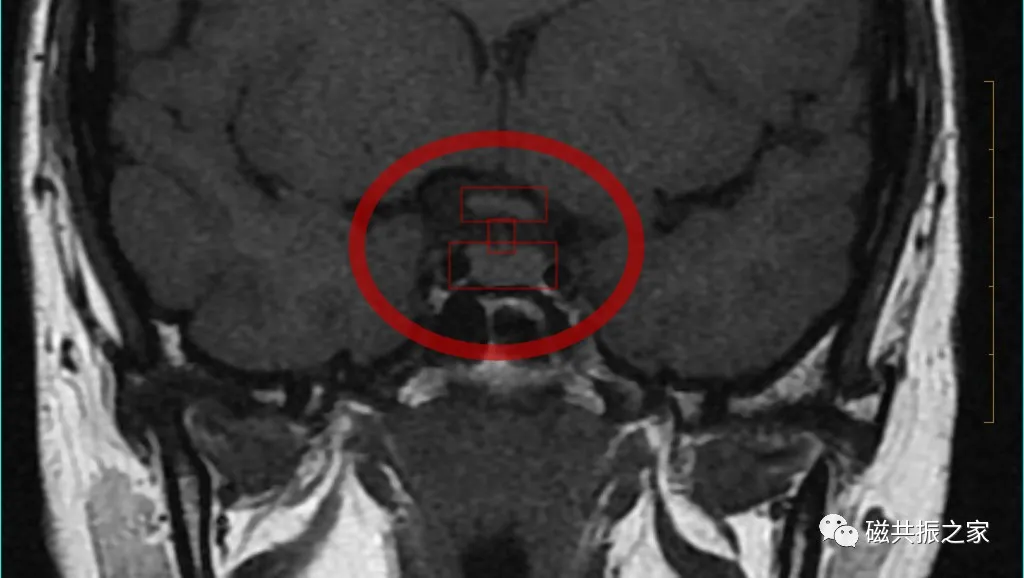

最理想的冠状位图像:同一层面视交叉、垂体柄和垂体均能清晰显示,共同组成“工”字结构。

以矢状位和横断位作为参考定位。在矢状位上定位线垂直于鞍底(或平行于垂体柄或垂直于垂体窝),在横断位上与大脑纵裂垂直,双侧对称扫描,扫描范围包括整个垂体,根据病变大小调整范围,需包括整个病变范围。

冠状位是观察垂体柄形态和测量垂体高度最理想的方位。